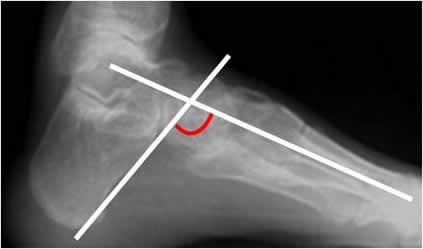

Angulo del pie plano:

Trazado en la Rx lateral. Se mide por la intersección de una línea que va desde la parte mas inferior de la tuberosidad del calcáneo, hasta la parte mas inferior de la articulación calcaneocuboidea y otra que pasa por el eje diafisiario del 1º metatarsiano. (Angulo de Rocher). Su valor normal es de 140º. (1). (Fig 94).

Si el valor es inferior se considera pie cavo y para cifras superiores, pie plano. (Fig 95 y 96).

Fig 94. Angulo del pie plano.

Rx lateral. Angulo de pie plano normal.

Fig 95. Pie cavus.

Rx lateral. Disminución del ángulo plantar, por pie cavus.

Fig 96. Pie plano.

Rx lateral. Aumento del ángulo plantar, por pie plano.